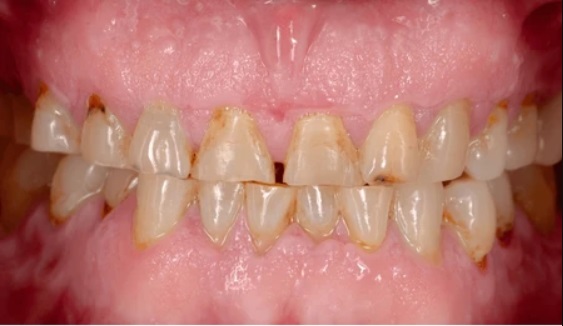

Enamel erosion, also known as enamel loss or dental erosion, refers to the gradual wearing away of the outer layer of your teeth – the enamel. Enamel is the hardest substance in the human body and serves as a protective barrier for your teeth. It shields the underlying dentin and pulp from exposure to bacteria, acids, and temperature changes.

Effects of Enamel Erosion on Oral Health

Enamel erosion can have significant implications for your oral health if left untreated. The gradual loss of enamel can lead to a range of dental problems, including:

- Tooth sensitivity:

Exposed dentin can result in heightened sensitivity, making it uncomfortable to consume hot, cold, sweet, or acidic foods and drinks.

- Tooth decay:

With the protective enamel layer compromised, bacteria can easily penetrate the tooth’s surface, leading to decay and cavities.

- Tooth discolouration:

As the enamel thins, the yellowish dentin beneath becomes more visible, causing the teeth to appear discoloured.

- Tooth loss:

In severe cases of enamel erosion, the teeth may become weak and brittle, increasing the risk of tooth loss.

- Gum problems:

Enamel erosion can also affect the gum tissue, leading to inflammation, gum recession, and gum disease.